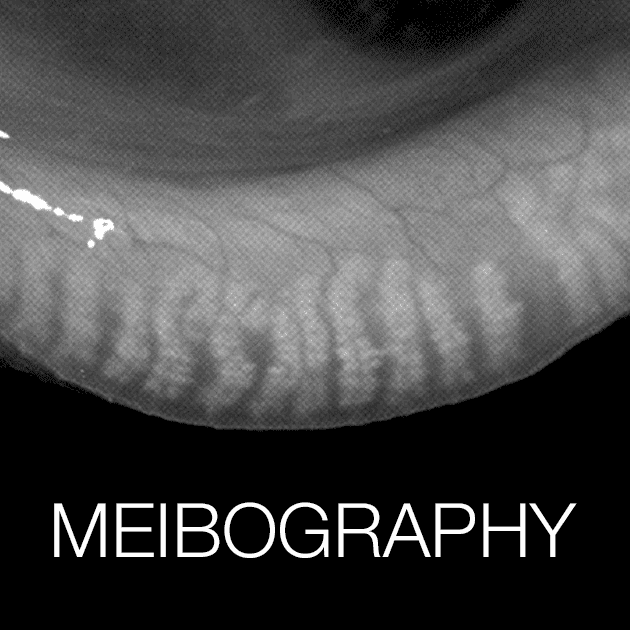

Demodex mites are tiny, worm-like parasites that live on the skin, including the skin around the eyes. There are two main species of Demodex mites that affect humans: Demodex folliculorum and Demodex brevis. Demodex folliculorum are typically found in the hair follicles and sebaceous glands of the skin, while Demodex brevis are typically found in the meibomian glands (glands that produce oil to keep the surface of the eye lubricated) and the sebaceous glands of the eyelids.